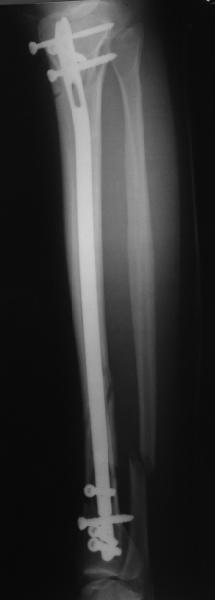

Сделали все-таки стержнем. На всякий случай просверлил дополнительное проксимальное отверстие, так что получилось три 45-градусных винта.

В дистракторе провеи спиц поболше в прокисмальном отделе, чтобы не разобщить фрагменты при сгибании колена. Комментарии и критика приветствуются.

We proceeded with nailing using a small wire distractor, with few wires at the proximal end to prevent displacement with forced knee flexion. Images attached. Comments and critics are welcome.

It is often a problem nailing upper tibial fractures. There is a tendency to apex anterior angulation as well as valgus alignment. Your entry point on the AP view seems to have been kept the same. How did you manage to maintain alignment? Any intra-operative pictures of your technique?

The lateral view shows your entry point to be quite posterior and I think this is recommended to avoid anterior angulation. Were you concerned about intra-articular penetration?

Overall an excellent post-op x-ray. Well done.

As i mentioned a small wire distractor was used. In common upper fractures it is enough to insert 2 frontal wires to the proximal fragment - one in the upper posterior aspect of the tibia and the second anteriorly and a bit more distally. The technique allows to avoid such known tricks like more lateral entry point, semi-extended knee, extended approach, using of bone clamps, plating with monocortical screws etc.

In this particlar case 4 frontal wires were inserted in anterior and posterior aspects at both sides of proximal fracture, and fixed to a single half ring with some bend to provide compression with wire tension. Image attached.

You are absolutely right, and the entry point could be more anterior without the risk of angulation. This a bit posterior placement was caused by the proximal anterior wire. No obvious problem with the knee though.